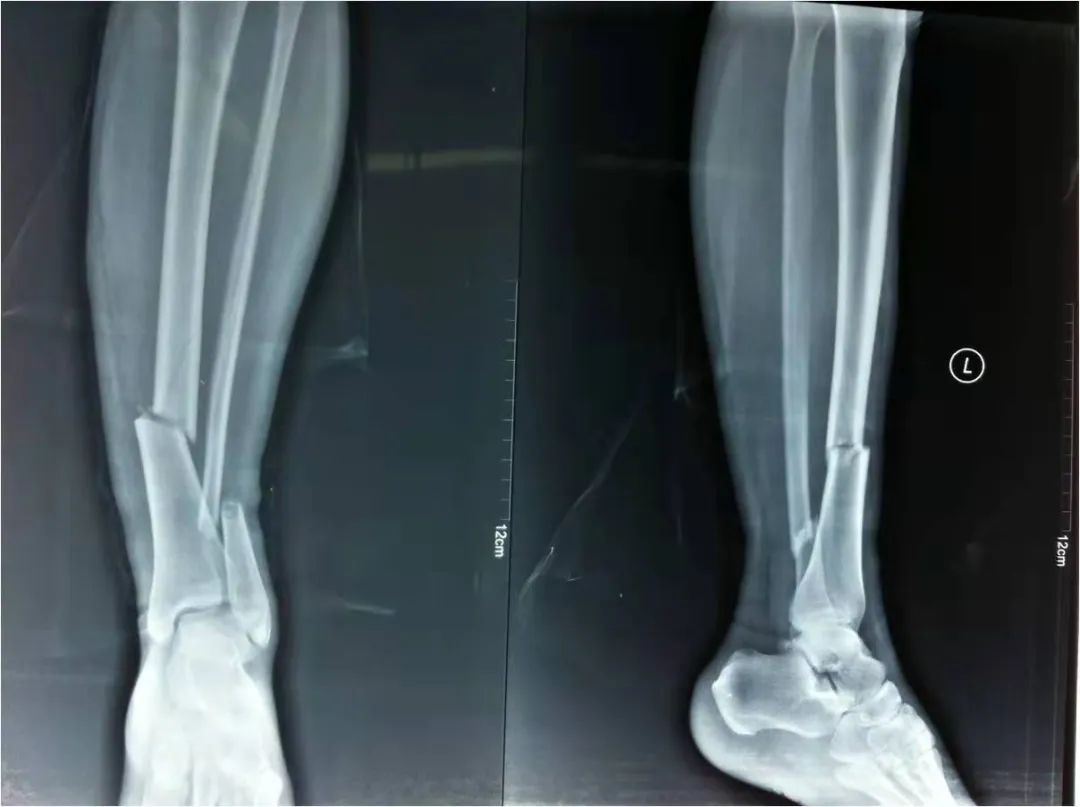

2022年4月22日,我院急救中心接診了一名骨折患者:患者在家不慎摔倒,導致剛做完手術沒多久的脛腓骨再次受創(chuàng),疼痛劇烈傷情加重。骨科呂國福主任迅速給予夾板外固定治療,并給予止疼治療減輕患者疼痛。經診斷患者脛腓骨粉碎性骨折明確,且第一次接骨板釘?shù)廊钥梢?,如不及時手術可能出現(xiàn)骨斷端外露發(fā)展為開放性骨折,可能出現(xiàn)骨筋膜室綜合癥。

如采用傳統(tǒng)手術需大范圍剝離軟組織,手術切口在18公分,損傷面大,影響骨折愈合。經過科內術前討論后與患者及家屬溝通后,呂國福主任決定行小切口微創(chuàng)鈦板植入內固定手術治療,術中植入內固定物并剝離軟組織,此方法對周圍皮膚破壞小,手術切口最小僅0.5公分,極大降低皮膚壞死及后期出現(xiàn)骨不連發(fā)生幾率,從而達到解剖復位。